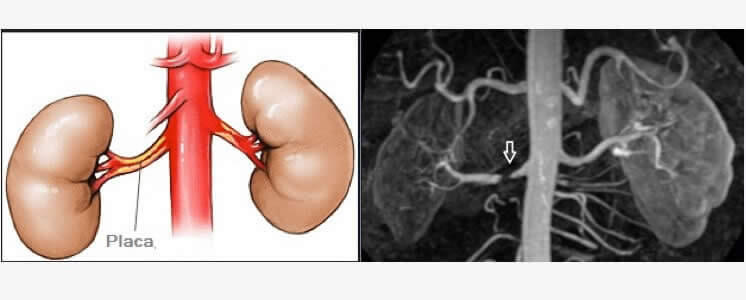

Doença Renal Crônica

Uma das causas da doença renal crônica ocorre se uma placa de ateroma reduzir o fluxo de sangue nas artérias renais. A redução do fluxo arterial para os rins pode acarretar hipertensão arterial de causa vascular. Ao longo do tempo, a doença renal crônica causa uma lenta perda da função renal. A principal função dos rins é remover os resíduos e a água em excesso do corpo. A doença renovascular causa hipertensão arterial sistêmica (HAS) de origem secundária, variando, segundo alguns autores, de 1% a 4% na população geral. A aterosclerose sistêmica é sua maior causa e responsável por danos em vários sítios, como lesões periféricas, cerebrovasculares, carotídeas e em artérias coronárias. Podemos definir hipertensão renovascular (HR) como uma condição clínica secundária a um estado de redução da perfusão renal, decorrente de um estreitamento do calibre da artéria renal maior que 60%.